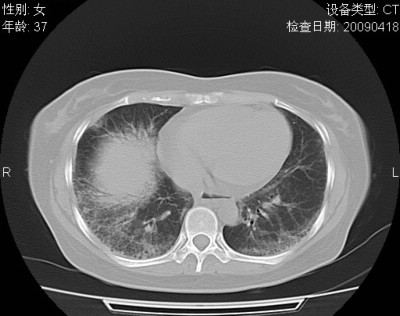

以下是引用随光逐影在2009-4-20 8:03:00的发言:[br]两肺间质性病变(间质性肺炎?特发性肺间质纤维化?)。

以下是引用51736011在2009-4-21 16:24:00的发言:[br]两肺间质性病变(间质性肺炎?特发性肺间质纤维化?)。